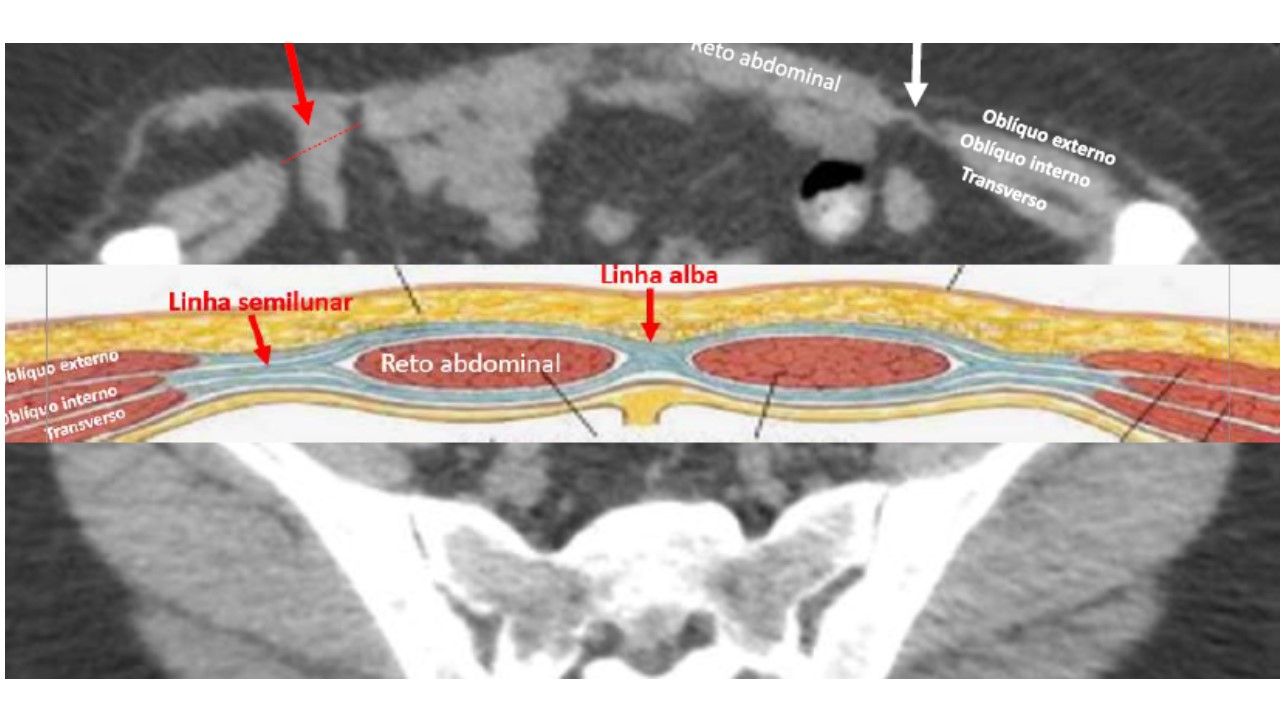

Imagem 11

ANATOMIA DA PAREDE ABDOMINAL E HÉRNIA DE SPIGELIAN

10/08/2020 14:35

Ler Mais